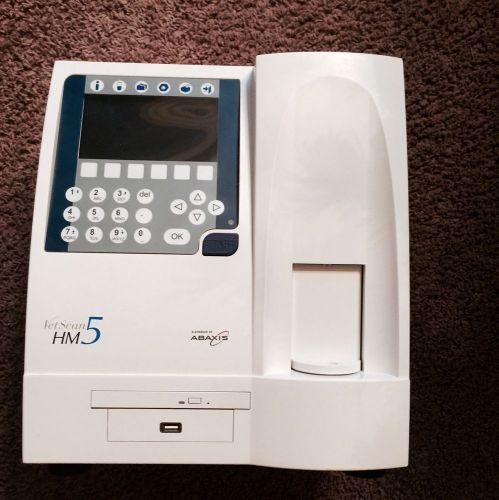

ABAXIS VETSCAN HM5 VETERINARY HEMATOLOGY BLOOD ANALYZER CBC RBC